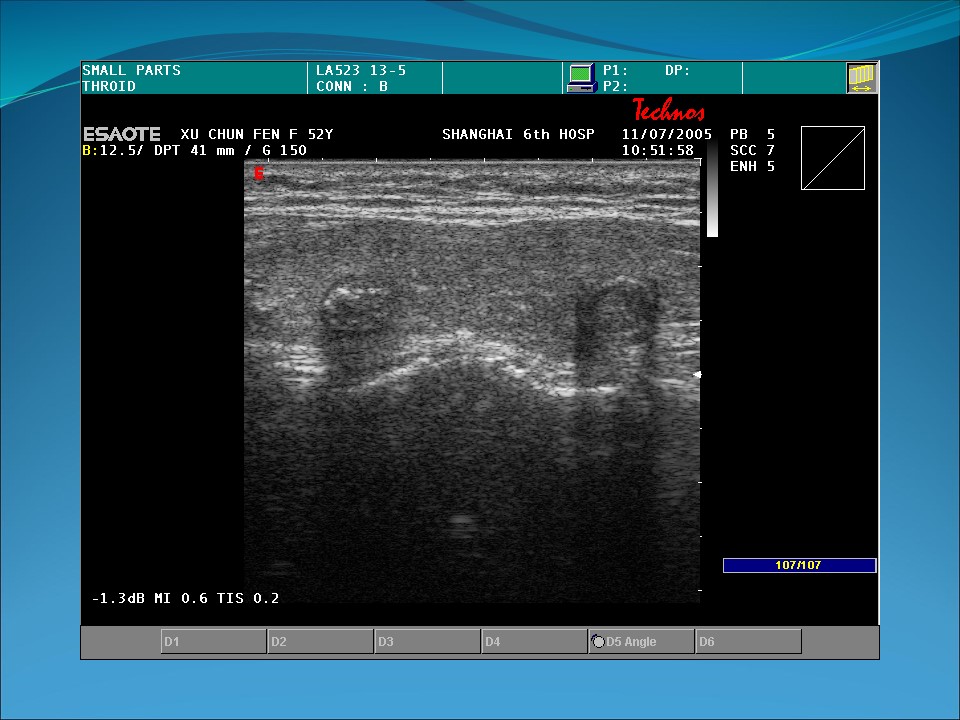

声像图特点:

1、两侧乳房增大,但边界光滑、完整。

2、内部质地和结构紊乱,回声分布不均,呈粗大的光点和光斑。

3、如有囊性扩张,乳房内见大小不等的无回声区,其后壁回声稍增强。